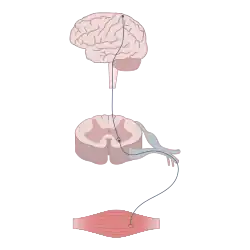

Electrical neuromodulation has three subcategories: deep brain, spinal cord, and transcranial, each aiming to treat specific conditions. Deep brain stimulation involves electrodes being surgically implanted into specific sections of the brain that are commonly responsible for movement and motor control deficiencies and disorders like Parkinson's and tremors. Spinal cord stimulation works by being placed near the spinal cord to send electrical signals through the body to treat various forms of chronic pain like lower back pain and CRPS. This form of neuromodulator treatment is considered one of the more high-risk treatments because of its manipulation near the spinal cord. Transcranial magnetic stimulation is slightly different in that it utilizes a magnetic field to generate electrical currents throughout the brain. This treatment is widely used to remedy various mental health conditions like depression, obsessive-compulsive disorder, and other mood disorders.[50]

Neuromodulation is often used as a treatment mechanism for moderate to severe migraines by way of nerve stimulation. These treatments work by utilizing the basic ascending pathways. There are three main modes. It works by connecting a device to the body that sends electrical pulses directly to the affected site (Transcutaneous Electrical Nerve Stimulation), directly to the brain (invasive electrical Neurotherapy techniques), or by holding a device close to the neck that works to block pain signals modulation from the PNS to the CNS.[51][52] and sends two of the most notable modes of that treatment, which are electrical and magnetic stimulation. Electrical nerve stimulation and some of the characterizations include transcranial alternating stimulation and transcranial direct current stimulation. The other is magnetic stimulation, which includes single pulse and repetitive transcranial stimulation.